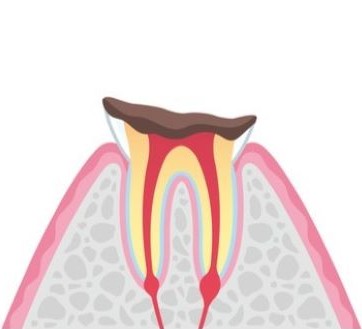

C3

C3段階では、むし歯が神経(歯髄)にまで達しているため、ズキズキする痛みが続きます。冷たいものや熱いものに敏感になり、夜間も眠れないほどの痛みを引き起こすことがあります。この段階の治療では、根管治療が必要です。当院では、ラバーダムを使用して治療中の唾液や細菌の侵入を防ぎ、徹底した消毒を行います。(※ラバーダムの使用は、症例によって異なります。)

C3段階では、むし歯が神経(歯髄)にまで達しているため、ズキズキする痛みが続きます。冷たいものや熱いものに敏感になり、夜間も眠れないほどの痛みを引き起こすことがあります。この段階の治療では、根管治療が必要です。当院では、ラバーダムを使用して治療中の唾液や細菌の侵入を防ぎ、徹底した消毒を行います。(※ラバーダムの使用は、症例によって異なります。)

C4では、歯の大部分が失われ、神経が死んでいるため痛みは一時的に感じませんが、膿が溜まりやすく、顎の腫れや強い痛みを引き起こします。場合によっては周囲の骨が溶け出し、隣接する歯にも影響が及ぶことがあります。抜歯が必要な場合も多く、その後はインプラント、ブリッジ、入れ歯などで咀嚼機能を回復させます。

C4では、歯の大部分が失われ、神経が死んでいるため痛みは一時的に感じませんが、膿が溜まりやすく、顎の腫れや強い痛みを引き起こします。場合によっては周囲の骨が溶け出し、隣接する歯にも影響が及ぶことがあります。抜歯が必要な場合も多く、その後はインプラント、ブリッジ、入れ歯などで咀嚼機能を回復させます。